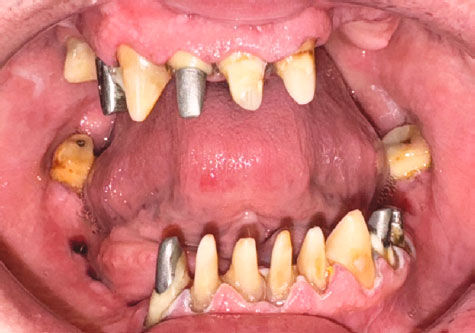

Пациент Б., 57 лет, обратился с жалобами на нарушение жевания из-за отсутствия зубов и на неудобное положение нижней челюсти. Из анамнеза: 9 лет назад пациенту на верхней и нижней челюстях были установлены дентальные имплантаты «Nobel» (Nobel Biocare, Швейцария), которые со временем дезинтегрировались (рис. 1, 2).

Рис. 2. Зубные ряды пациента в вынужденном положении нижней челюсти

Fig. 2. Patient’s teeth with a forced position of the mandible